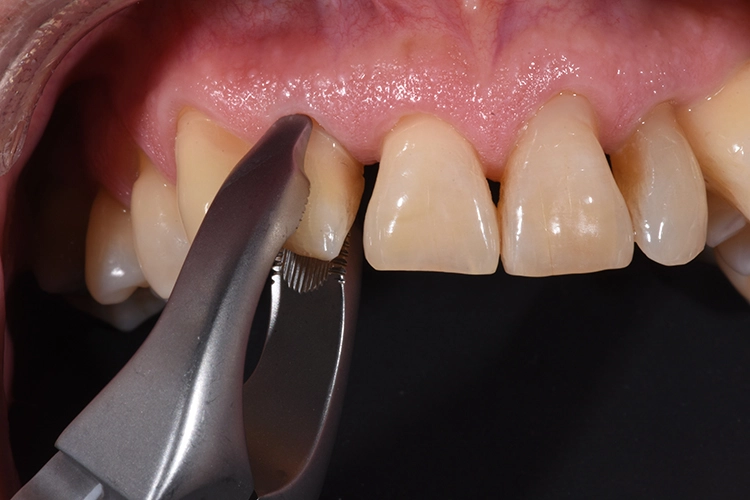

Die Zahnextraktion muss in jedem Fall äußerst schonend und atraumatisch erfolgen, um die auf dem Wurzeldentin anhaftenden Zellen nicht zu schädigen, hierbei haben sich diamantierte Zangen oder – bei subkrestal frakturierten Zähnen – das Benex-System bewährt [12]. Auch sollte der Zahn vor dem Austrocknen geschützt werden, weshalb es sich bewährt hat, den Zahn eventuell in einer Zahnrettungsbox zwischen zu lagern. Anschließend wird der Zahn in der neuen Position mittels TTS Schiene oder lichthärtendem Glasfasermaterial an die Nachbarzähne geschient.

Anschließend wurde der durch die externe Resorption stark angegriffene Wurzelrest schonend entfernt. Bei der Sofortimplantation kommt es auf den Erhalt der lokalen knöchernen Bedeckung an.